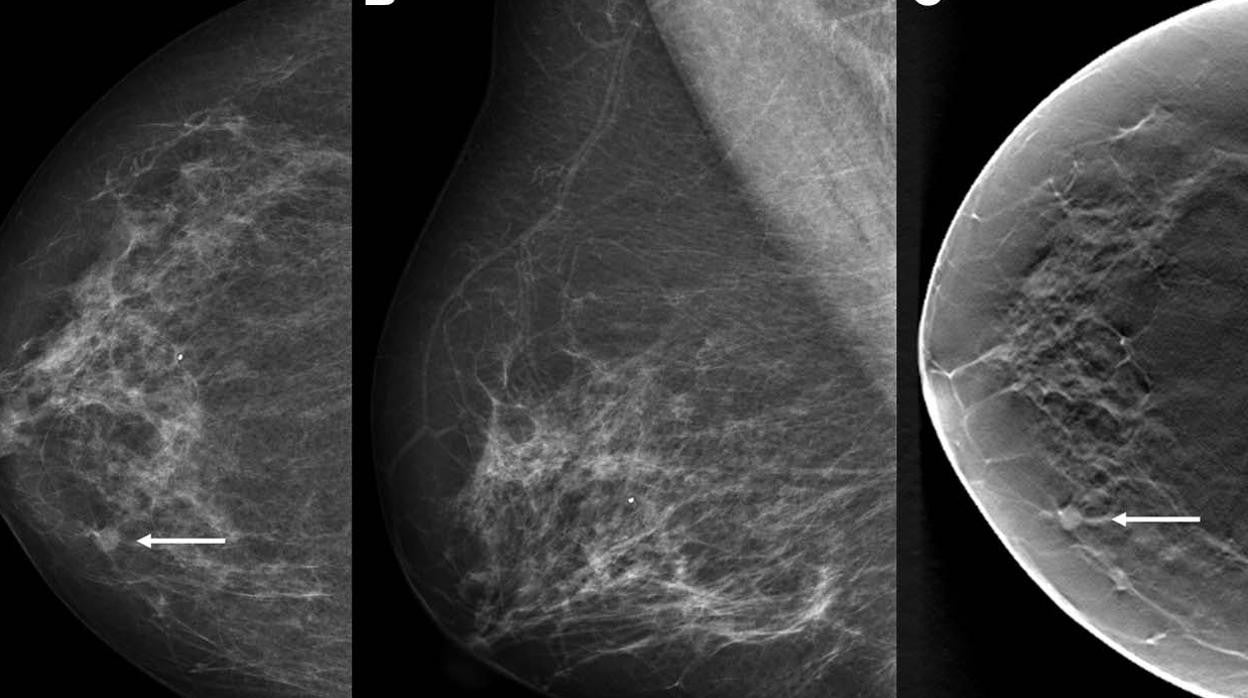

Imágenes de una mujer de 68 años con carcinoma dúctal in situ detectado por cribado con una puntuación de inteligencia artificial (IA

R.I.